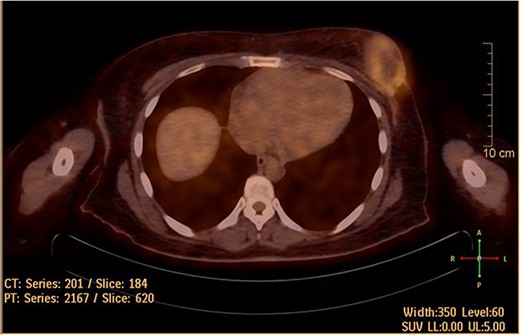

The patient was referred to medical oncology clinic. On exam, she had an eastern cooperative oncology group-performance status of zero, was in pain from her left breast. Assessment of the breast lump revealed a palpable, huge left breast mass, hard in consistency, around 10 cm in largest diameter. There were no palpable lymph nodes in the left axilla. Examination of the right breast was unremarkable. The affected breast is shown in Fig. 1. Otherwise, her chest and abdomen exam were unremarkable, with no lower limb edema. Baseline chest-abdomen–pelvis computed tomography (CT), shown in Fig. 2, showed a large left breast mass 8.0× 2.0 × 4.7 cm with diffuse skin thickening, few axillary lymph adenopathy, the largest of which measured 1.9 cm (shown in Fig. 3), with no distant metastasis. No magnetic resonance imaging was obtained prior to treatment as it was unavailable at the institute. The case was discussed by a multidisciplinary team of medical oncologists, radiation oncologists, surgical oncologists and pathologists. The final decision was that the patient should be treated as a case of high-grade sarcoma, so she was started on ifosfamide–adriamycin (IA) protocol (ifosfamide, 2500 mg/m2, mesna, 800 mg/m2 and doxorubicine, 75 mg/m2 intravenous (IV) for 3 days) as neoadjuvant, to be followed by surgery and adjuvant radiotherapy and chemotherapy. Paraffin blocks were requested by the pathologists for case revision at our institute.

She underwent positron emission tomography/computed tomography after the sixth cycle, shown in Fig. 6. It showed a left breast hypermetabolic mass, compatible with known primary disease, there was no previous study for comparison, however, comparison with previous CT showed marked interval morphological regression of the tumor, no hypermetabolic lymph nodes, with no distant metastasis. Follow up breast ultrasound showed multifocal multicentric left breast lesions with few suspicious left axillary lymph nodes. The patient was seen in the surgical oncology outpatient clinic and prepared for mastectomy.

Hypermetabolic left breast mass in last positron emission tomography/computed tomography, following six cycles of IA.